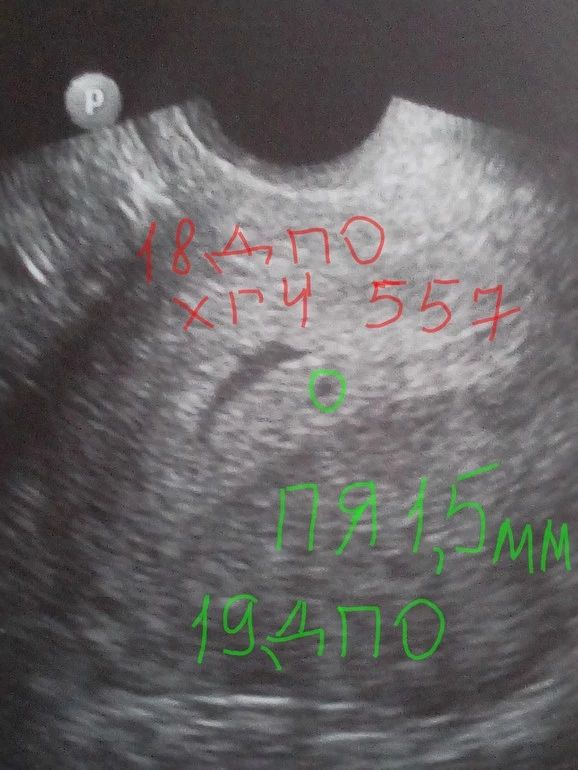

В 4+4 плодное яйцо 1,5 мм Изображение В 5+4 плодное яйцо 10 мм, эмбрион 1 мм Изображение В 6+4 был эмбрион 7,7 мм и сердцебиение было

Ну естественно пя 14 мм это не на 4 акушерских,в 4 акушерских хгч 100-300 едениц,никакого пя по узи не видно,ваше УЗИ на 4 от зачатия и 6 акушерских

Мне на первом УЗИ в 5 акушерских пя было 8 мм,поставили 3 недели,ну логически 3 акушерских это неделя до задержки,какое может быть пя,там тесты ещё беременности не показывают